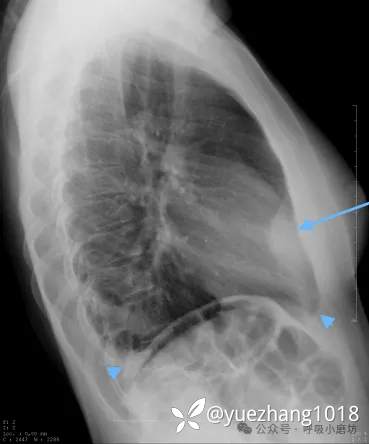

初始后前位胸片未见异常,但侧位片提示胸骨后肿块及左侧少量胸腔积液(图1A)。

图1A 胸部侧位X线摄影: 箭头指向胸骨后肿块;箭标示处指向胸腔积液

考虑到产后情况和D-二聚体轻度升高,完善了CTPA检查,未发现肺栓塞。但于左心膈角见一脂肪密度病灶,周围环绕炎性组织(图1B)。

图1B CTPA显示左心膈角处一脂肪性病变(箭头),周围环绕炎性组织,伴有少量胸腔积液(箭)

经非甾体抗炎药治疗后症状迅速缓解,2周后复查CT显示病灶基本吸收(图1C)。

图1C 两周后CTPA:左心膈角处病灶(箭头所示)已基本完全消退,未见胸腔积液